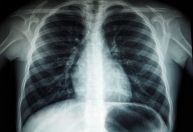

O Brasil tem uma média de 5 mil mortes por tuberculose todos os anos e o combate à doença é um desafio para o País.

Ela lembra, porém, que o País está entre as 30 nações que mais concentram casos de tuberculose no mundo.

“A doença atinge de forma desproporcional as populações mais vulneráveis socialmente, que não tem acesso à moradia e alimentação, por exemplo”, explicou.

“Estamos com os mesmos indicadores de mortalidade de 10 anos atrás, as pessoas têm chegado com quadros mais graves”, disse.